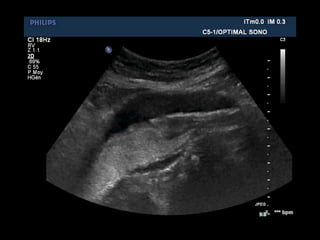

ÉVOLUTION DU CALIBRE

Coupes 2D transverses étagées

• incidence perpendiculaire à l’axe aortique

section circulaire

• mesure du diamètre antéropostérieur externe

maximal, moyenne de 3 mesures

ÉVOLUTION DU CALIBRE Coupes2D transverses étagées • incidence perpendiculaire à l’axe aortique section circulaire • mesure du diamètre antéropostérieur externe maximal, moyenne de 3 mesures